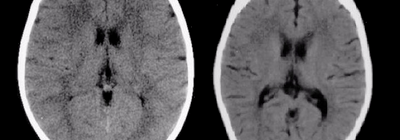

The brain scan on the left is of a child nurtured in a healthy environment. The brain scan on the right is of a severely neglected child who had a variation of total global neglect (similar […]